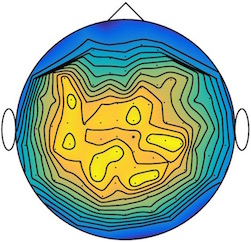

We applied our method to a magnetoencephalography (MEG) dataset. In this setup, brain activity of a subject is recorded (Elekta Neuromag, 306 sensors of which 204 planar gradiometers and 102 magnetometers, sampling frequency 1000Hz) while the subject reacted to the presentation of a target stimulus by pressing either the left or the right button.

Data is preprocessed applying signal space separation correction, interpolation of noisy sensors, and realignment of data into a subject-specific head position (MaxFilter, Elekta Neuromag). The signal was then filtered (low pass 40HZ), and artifacts such as blinks and heartbeats removed thanks to Signal-Space Projection using the Brainstorm software222http://neuroimage.usc.edu/brainstorm. The samples we used for our barycenter computations are an average of the norm of the two gradiometers for each channel from stimulation onto 50ms and the classes were left or right button.

| Class 1 | Class 2 | ||||||

|

|

|

|

|

|

|

|

| Sample 1 | Sample 2 | Sample 3 | Mean | Sample 1 | Sample 2 | Sample 3 | Mean |

|

|

|

|

|

|

|

|

This results in two classes of recordings, one for each pressed button. We aim at computing a representative activity map for each class using Wasserstein barycenters. For each class we have recordings each having samples located on the vertices of an hexahedral mesh of a hemisphere (corresponding to a MEG recording helmet). These recorded values are positive by construction, and we rescale them linearly to impose . Figure 6, top row, shows some samples from this dataset, displayed using interpolated colors as well as iso-level curves. The black dots represent the position of the electrodes on the half-sphere of the helmet, flattened on a 2-D disk.

We computed TV-regularized barycenters independently for each class by solving (16) with the TV regularization using the projected gradient descent method (22). We used a squared Euclidean metric (24) on the flattened hemisphere. Since the data is defined on an irregular graph, instead of (23), we use a graph-based discrete gradient. We denote the graph which connects neighboring electrodes. The gradient operator on the graph is

The total variation on this graph is then obtained by using , the norm, i.e. we use in (23).

Figure 6 compares the naive barycenters (i.e. the usual mean), barycenters obtained without regularization (i.e. ) and barycenters computed with an increasing regularization strength . The input histograms being very noisy, the use of regularization is important to make the area of significant activity emerge from the noise. The use of a TV regularization helps to keep a sharp transition between active and non-active regions.